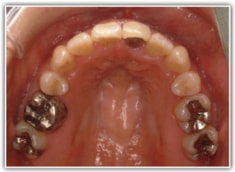

治療後(2年3ヶ月後)

歯根のパラレリング(平行性)が獲得されております。

下顎8番は、両側抜歯済みです。

顎位は良好な状態です。